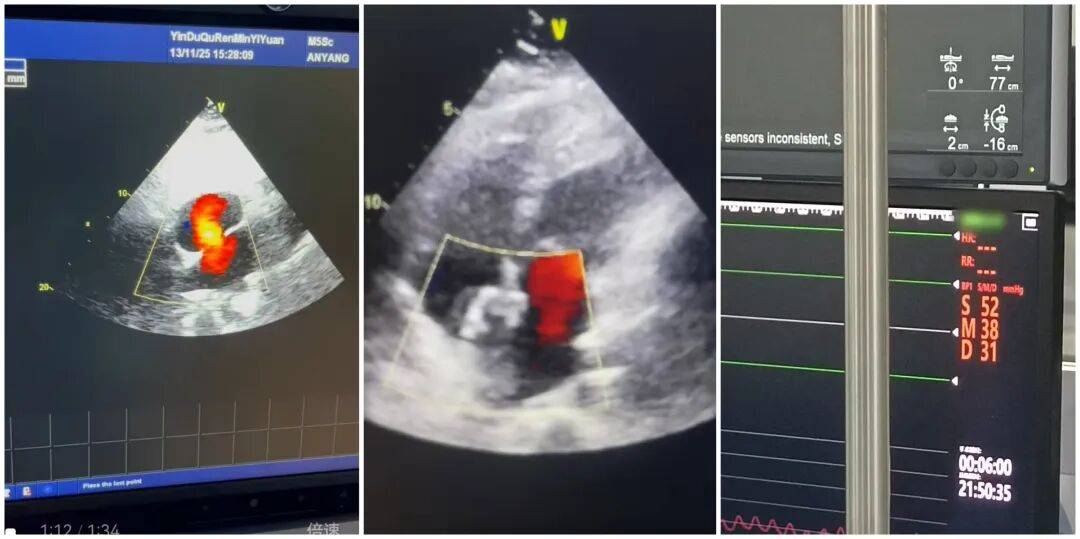

患者入院后,心血管內(nèi)科團(tuán)隊(duì)高度重視,立即組織多學(xué)科會診,結(jié)合心臟超聲、心電圖等詳細(xì)檢查結(jié)果,與特邀專家共同研判病情,制定了精準(zhǔn)的個(gè)性化手術(shù)方案。11月14日手術(shù)當(dāng)天,經(jīng)右心導(dǎo)管檢查顯示,路女士的肺動脈壓已高達(dá)52mmHg,需盡快干預(yù)。在團(tuán)隊(duì)的密切配合與專家的精準(zhǔn)指導(dǎo)下,手術(shù)歷時(shí)36分鐘順利完成,成功對其直徑約25mm的室間隔缺損進(jìn)行封堵。術(shù)后即刻超聲檢查證實(shí),缺損處無過隔血流,手術(shù)效果達(dá)到預(yù)期。